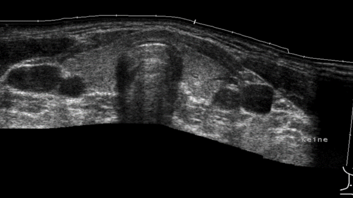

Im Rahmen der Schilddrüsenbehandlungen und Schilddrüsendiagnostik in der HNO-Klinik nimmt die Sonografie einen großen Stellenwert ein. So können Aussagen über das Volumen, die Risikoeinschätzung von Knoten (TIRADS), Elastografie sowie ultraschallgesteuerte Punktionen und Stanzbiopsien durchgeführt werden. Überdies hinaus ist der Ultraschall das zentrale Element bei der Thermoablation von Schilddrüsenknoten. Hierfür stehen uns Ultraschallgeräte der neuesten Generation zur Verfügung.